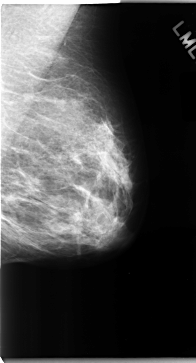

C_0091_1.RIGHT_MLO

RIGHT_MLO LINES 4744 PIXELS_PER_LINE 2624 BITS_PER_PIXEL 12 RESOLUTION 50 NON_OVERLAY